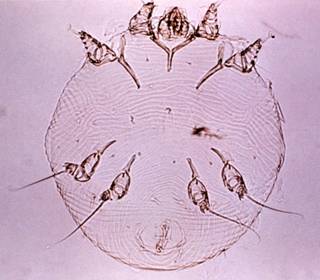

Scabies of Mange Mites. Sarcoptes scabei is a parasitic mite that

Similarly the scabies mites that attack dogs do no infest humans. The human scabies mite is almost invisible to

the naked eye (about 1/60 inch), cylindrical in shape, and has golf tee-shaped

suckers on the tips of the legs (Figure 5A).

Figure 5A. A female human sarcoptic

mange mite (Sarcoptes scabei) greatly magnified. Image courtesy of CDC Healthwise Photo Library.